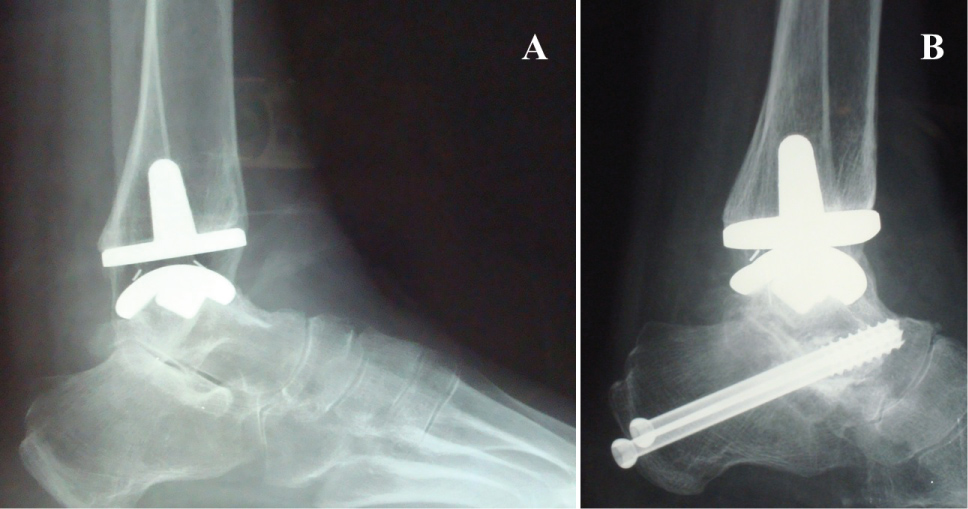

There were 2 intraoperative complications: one ankle sustained a fracture of the lateral malleolus and one ankle a fracture of the medial malleolus (Figure 6). The lateral malleolar fracture was treated non-operatively with a plaster boot in neutral position (90º of ankle flexion). The medial malleolar fracture underwent internal fixation surgery and then a plaster boot was applied (Figure 7). Complete healing occurred in 35 days in the first case and in 30 days in the second one.

Figure 6: Stable fracture of the lateral malleolus. Conservative treatment. View Figure 6

Figure 7: Unstable fracture of the medial malleolus. Postsurgical radiographs of internal fixation with screws A) AP view; B) Lateral view. View Figure 7

A total of 8 concomitant procedures were performed in 5 patients: 2 subtalar arthrodesis, 2 Achilles tendon lengthening, 3 malleolar osteotomies (1 lateral and 2 medial osteotomies), and 1 revision of the talar component for a presumable oversizing.

Wood, et al. defined the following additional procedures: reattachment of the anterolateral capsule, gastrocnemius recession, talonavicular fusion, calcaneal osteotomy and osteotomy of the first metatarsal [14]. Additional procedures can be performed both during the implant of TAR, if needed (contemporary additional procedures), or later, in relation to the clinical situation (subsequent additional procedures). In our series we preferred not to carry out contemporary procedures, instead performing a reoperation after the full recovery of ankle ROM and the eventual onset of pain or other disorders not previously manifested (Figure 8). It is essential to plan not only the possible associated surgical acts but also the time interval in which to achieve the second procedure.

Figure 8: A) Subtalar joint osteoarthritis onset 1 year after TAR; B) Subtalar arthrodesis, iliac allograft, 2 screws. No cyst, no radiolucency, no subsidence. View Figure 8